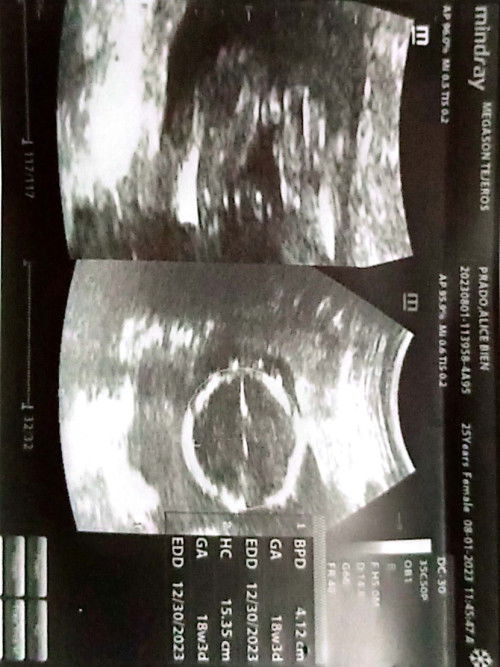

First time mom🫶

Satingin nyo ano po gender ni baby ko 💜🫶 18weeks pregnant po 💜